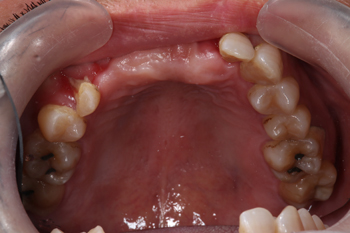

インビザラインGOによる前歯のデコボコ治療

前歯部叢生の方のインビザラインGOによる部分矯正

インビザラインに興味がありご来院された患者様です。まずはCTやパノラマ、iTeroにて精密資料取りを行っていきました。

Before

インビザラインGoによる部分矯正の適応範囲では下顎の歯が並ぶスペースの確保やクロスバイトという上下の歯の重なりが逆になっている不正咬合があるため判断の難しい症例ではありましたが、精密資料撮りによる診断や矯正専門医との連携診断、患者様のご希望も踏まえ、追加の歯列矯正が必要になる場合もあることをお伝えし、想定しながらインビザラインGoによる部分矯正にて進行することとなりました。

After

マウスピース矯正の期間と装着枚数が終了し、懸念していた箇所も順調に歯列が並んできましたが、想定している咬み合わせまでは歯列が動ききりませんでしたので、追加のマウスピースで進行していきます。

今後も患者様にアライナーをしっかりと1日つけていただくなどご協力いただきながら、整った歯並びを作り、また口腔内環境を永く維持していけるように担当医として努めていきます。

ガタガタに並ぶ歯並びの方は食べ物が詰まりやすい場合や歯磨きなどのセルフケアが行き届かず、むし歯や歯周病のリスクが高くなる場合もございます。気になる方はお気軽にご相談ください。

治療の内容 マウスピース型矯正装置(インビザラインGo)による部分矯正とホームホワイトニングによる治療

期間・回数 6ヶ月・7回(カウンセリング・検査含む)

費用 自由診療:マウスピース型矯正装置(部分矯正)+ホームホワイトニング 総額 450,000円(税込 495,000円)